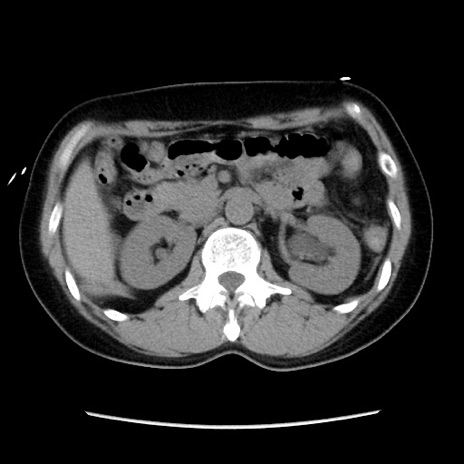

症例10(横断像)

【症例】 50歳代女性

【主訴】 腹痛

【現病歴】前日生レバーを食べた。今朝に排便あり。 昼前に突然発症の腹痛を生じ、当院救急外来を受診した。

【既往歴】 子宮筋腫にてで子宮全摘後

【身体所見】 意識清明、腹部:平坦、軟、下腹部やや左を中心に圧痛・反跳痛あり、筋性防御あり

【データ】WBC 7800、CRP 0.07